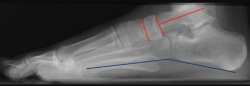

Para determinar el patrón anatómico del pie plano(3), se valora en la radiografía lateral en carga dónde está el vértice de la deformidad mediante los siguientes ángulos (Figura 7):

Figura 7. Radiografía lateral en carga de un pie normal. Ángulos utilizados para determinar el patrón anatómico del pie (rojo). El ángulo entre los puntos inferiores del calcáneo y el quinto metatarsiano (azul), si está disminuido, nos orienta para el diagnóstico de pie plano cavo.

• Ángulo entre el eje longitudinal del astrágalo y la superficie articular navicular (normal: 90°).

• Ángulo entre las superficies articulares del navicular y la superficie articular distal del primer cuneiforme (N1C) (normal: 0°).

• Ángulo entre los puntos inferiores del calcáneo y el 5° metatarsiano (normal: 160°).

Correlación radiológica de los patrones anatómicos con su orientación quirúrgica(3)

• PPV subtalar: se caracteriza por valgo subtalar sin abducción del antepié. En la radiografía lateral (Figura 8) el vértice del pie plano está en la articulación TN (ángulo eje astrágalo-superficie navicular disminuido). En este patrón, si el pie es flexible y con más de 2 años de crecimiento residual, está indicado realizar un procedimiento de limitación de la movilidad subastragalina.

Figura 8. Pie plano valgo (PPV) subtalar. Ángulo eje astrágalo-superficie navicular disminuido y C5M normal.

• PPV mediotarsiano: abducción y horizontalización del mediotarso sin evidencia radiológica de valgo subtalar, con acortamiento relativo de la columna externa del pie (Figura 9). El vértice del pie plano en la vista lateral está en la articulación naviculocuneiforme (ángulo N1C aumentado) y la abducción se mide en la radiografía DP por el ángulo C5M. La osteotomía de alargamiento del calcáneo (columna externa) es el procedimiento de elección.

Figura 9. Pie plano valgo (PPV) mediotarsiano. Ángulo N1C y C5M alterado.

• Patrón PPV mixto: combinación de valgo subtalar y mediopié en abducción. El vértice del pie plano en la vista lateral es compartido por las articulaciones TN y naviculocuneiforme. En la radiografía DP está aumentada la divergencia AC (subtalar) y el ángulo C5M (MT). La osteotomía de alargamiento del calcáneo corrige la abducción MT y el valgo subtalar.

• Patrón del pie plano cavo: combina una deformidad en cavo del arco lateral (columna lateral con arco aumentado) y hundimiento del arco medial. En la radiografía lateral en carga, el vértice del pie plano es variable y el ángulo entre los puntos inferiores del calcáneo y el quinto metatarsiano estará disminuido. La vista DP muestra una abducción moderada del mediopié.